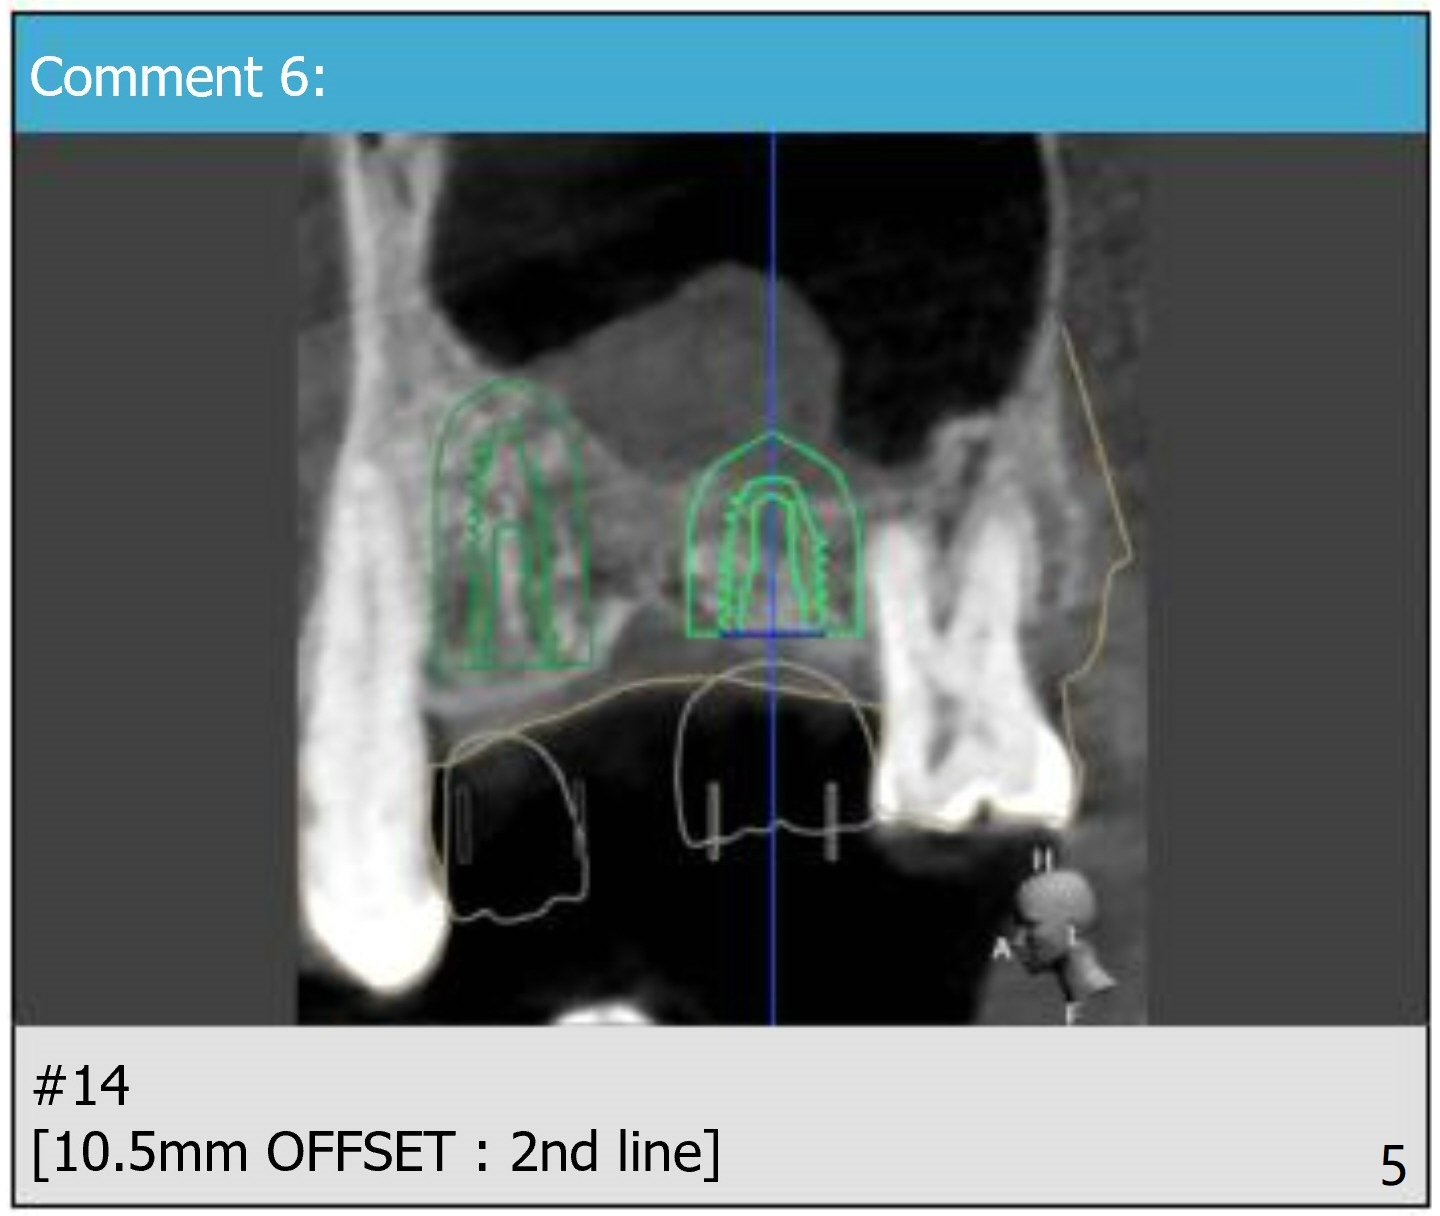

Return to Upper Molar Immediate Implant, Armaments